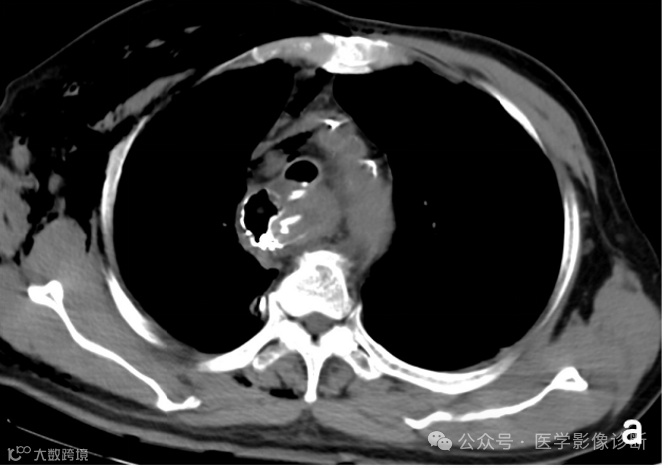

患者,男性,67岁,食管癌术后。

轴位 CT 显示食管癌术后变化(a, b)。然而,由于临床提供的申请表没有提醒,放射科医生只描述了术后变化,没有提及气管食管瘘。多平面成像(MPR)可以更好地显示瘘管。根据口服造影剂的使用情况,放射科医生应该明白医生想要观察是否发生了瘘管。